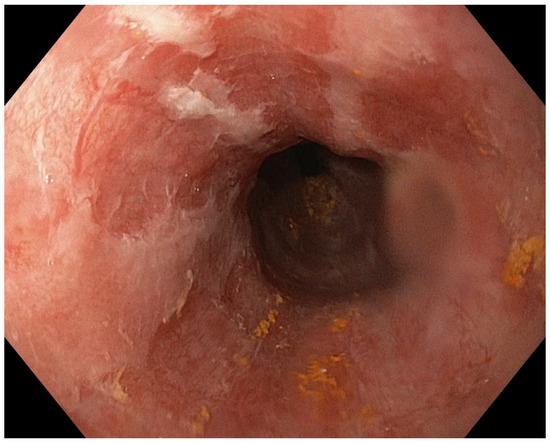

Acute Esophageal Necrosis in Acute Pancreatitis—Report of a Case and Endoscopic and Clinical Perspective

Grigore, M.; Enache, I.; Chirvase, M.; Popescu, A.L.; Ionita-Radu, F.; Jinga, M.; Bucurica, S. Acute Esophageal Necrosis in Acute Pancreatitis—Report of a Case and Endoscopic and Clinical Perspective. Diagnostics 2023, 13, 562. https://doi.org/10.3390/diagnostics13030562